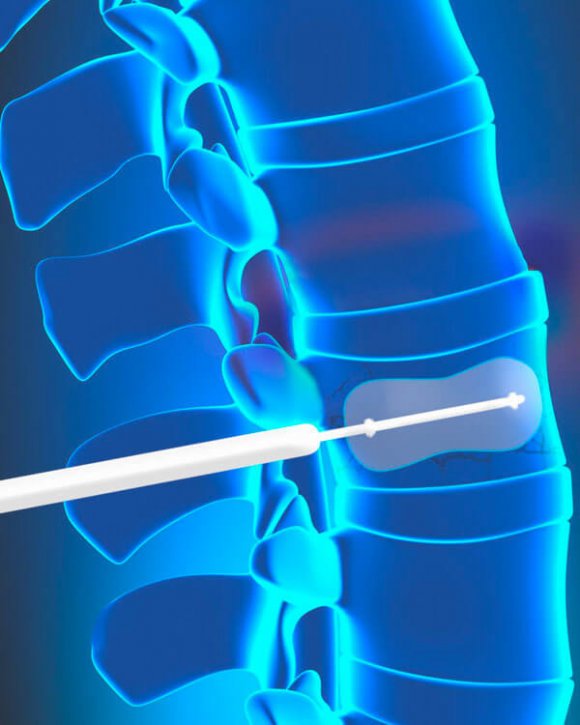

É feita uma incisão de aproximadamente 1 cm de comprimento. Usando uma agulha e a cânula (tubo), o especialista em coluna cria um pequeno caminho para dentro do osso fraturado. Um balão pequeno é guiado através do tubo no interior da vértebra. O procedimento é feito em ambos os lados do corpo vertebral.

Em seguida, os balões são inflados com cuidado em uma tentativa de aumentar as vértebras em colapso e devolvê-las à sua posição pré-fratura.

Numa tentativa para criar um vazio (cavidade), os balões são insuflados no corpo vertebral. Uma vez que o corpo vertebral se encontra na posição correta, o balão é esvaziado e retirado.

A cavidade é preenchida com cimento ósseo.